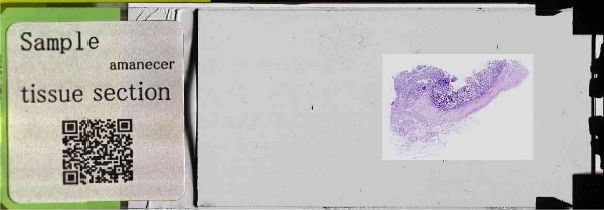

組織標本:腸管、アルシアン青-PAS重染色

対物レンズ倍率40倍、単層でスキャンされたデータです。